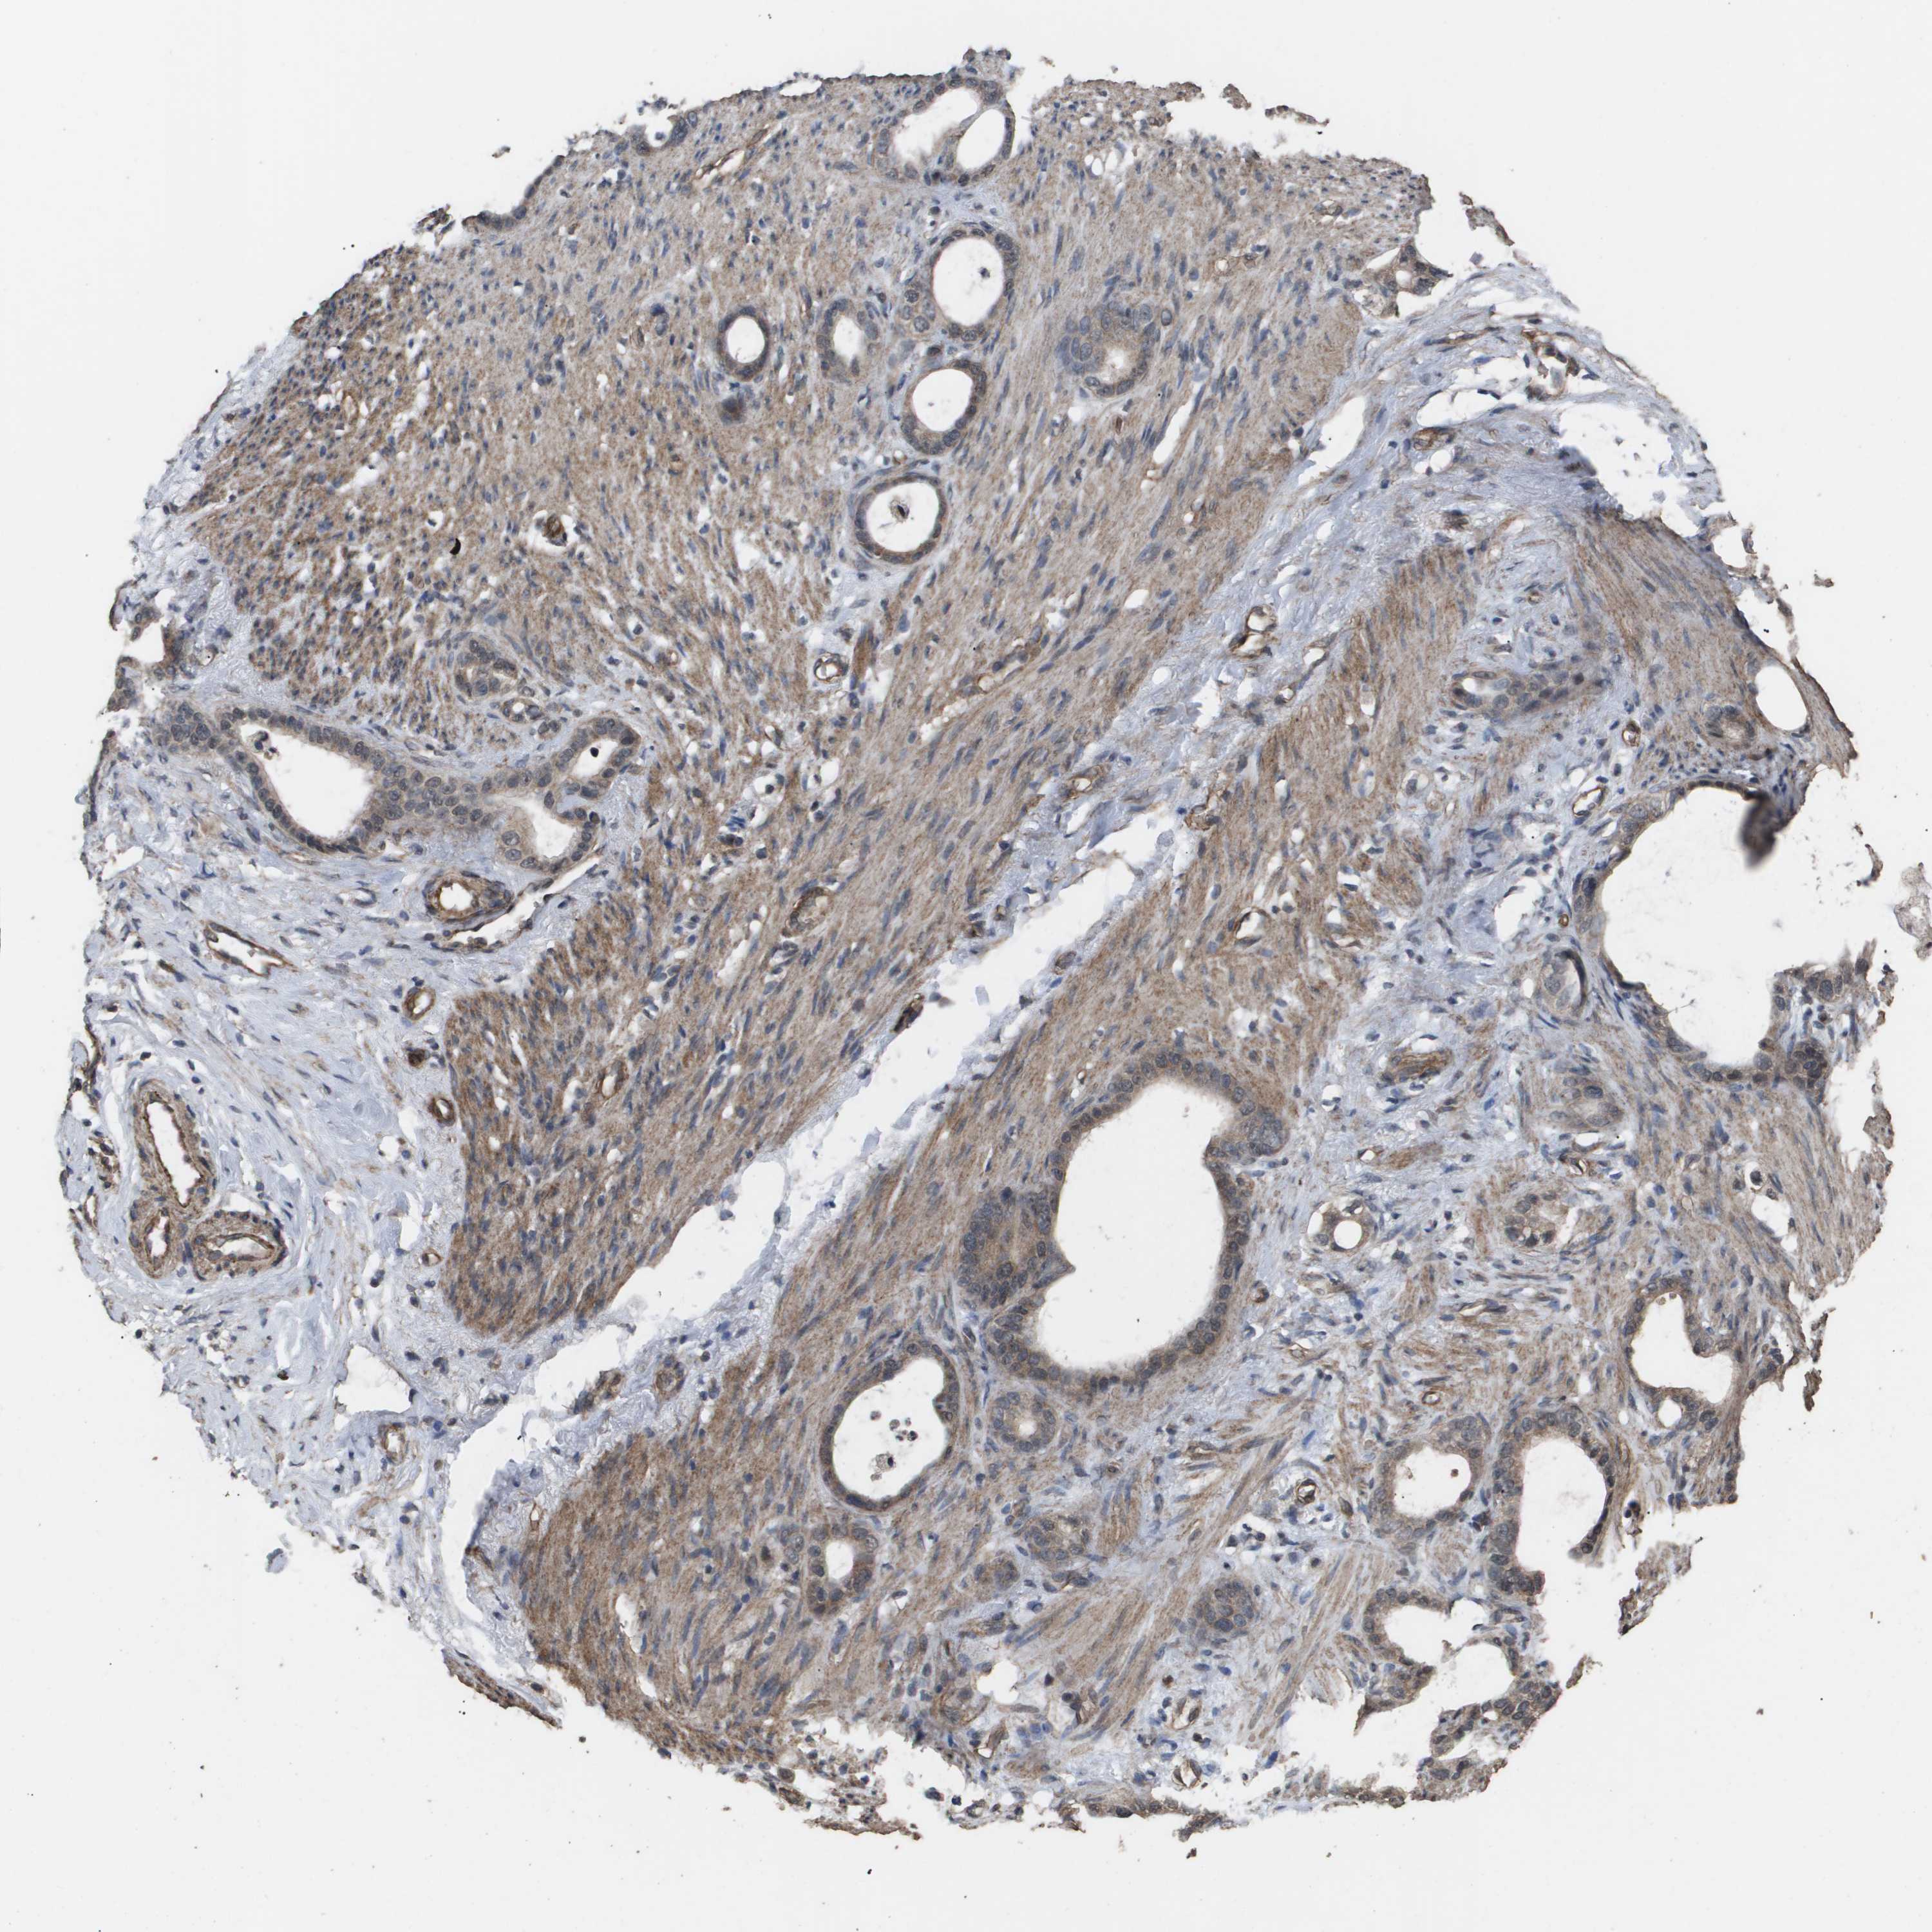

STOMACH CANCER - Protein expressioni

A mouse-over function shows sample information and annotation data. Click on an image to view it in a full screen mode. Samples can be filtered based on level of antibody staining by selecting one or several of the following categories: high, medium, low and not detected. The assay and annotation is described here.

Note that samples used for immunohistochemistry by the Human Protein Atlas do not correspond to samples in the TCGA dataset.

Antibody stainingi

Antibody staining in the annotated cell types in the current human tissue is reported as not detected, low, medium, or high, based on conventional immunohistochemistry profiling in selected tissues. This score is based on the combination of the staining intensity and fraction of stained cells.

Each image is clickable and will lead to virtual microscopy that enables deeper exploration of all samples and also displays staining intensity scores, fraction scores and subcellular localization as well as patient and tissue information for each sample.

Antibody HPA002185

Antibody CAB017787

Staining

High

Medium

Low

Not detected

Intensity

Strong

Moderate

Weak

Negative

Quantity

>75%

75%-25%

<25%

None

Location

Nuclear

Cytoplasmic/membranous

Cytoplasmic/membranous,nuclear

Adenocarcinoma, NOS

Adenocarcinoma, High grade